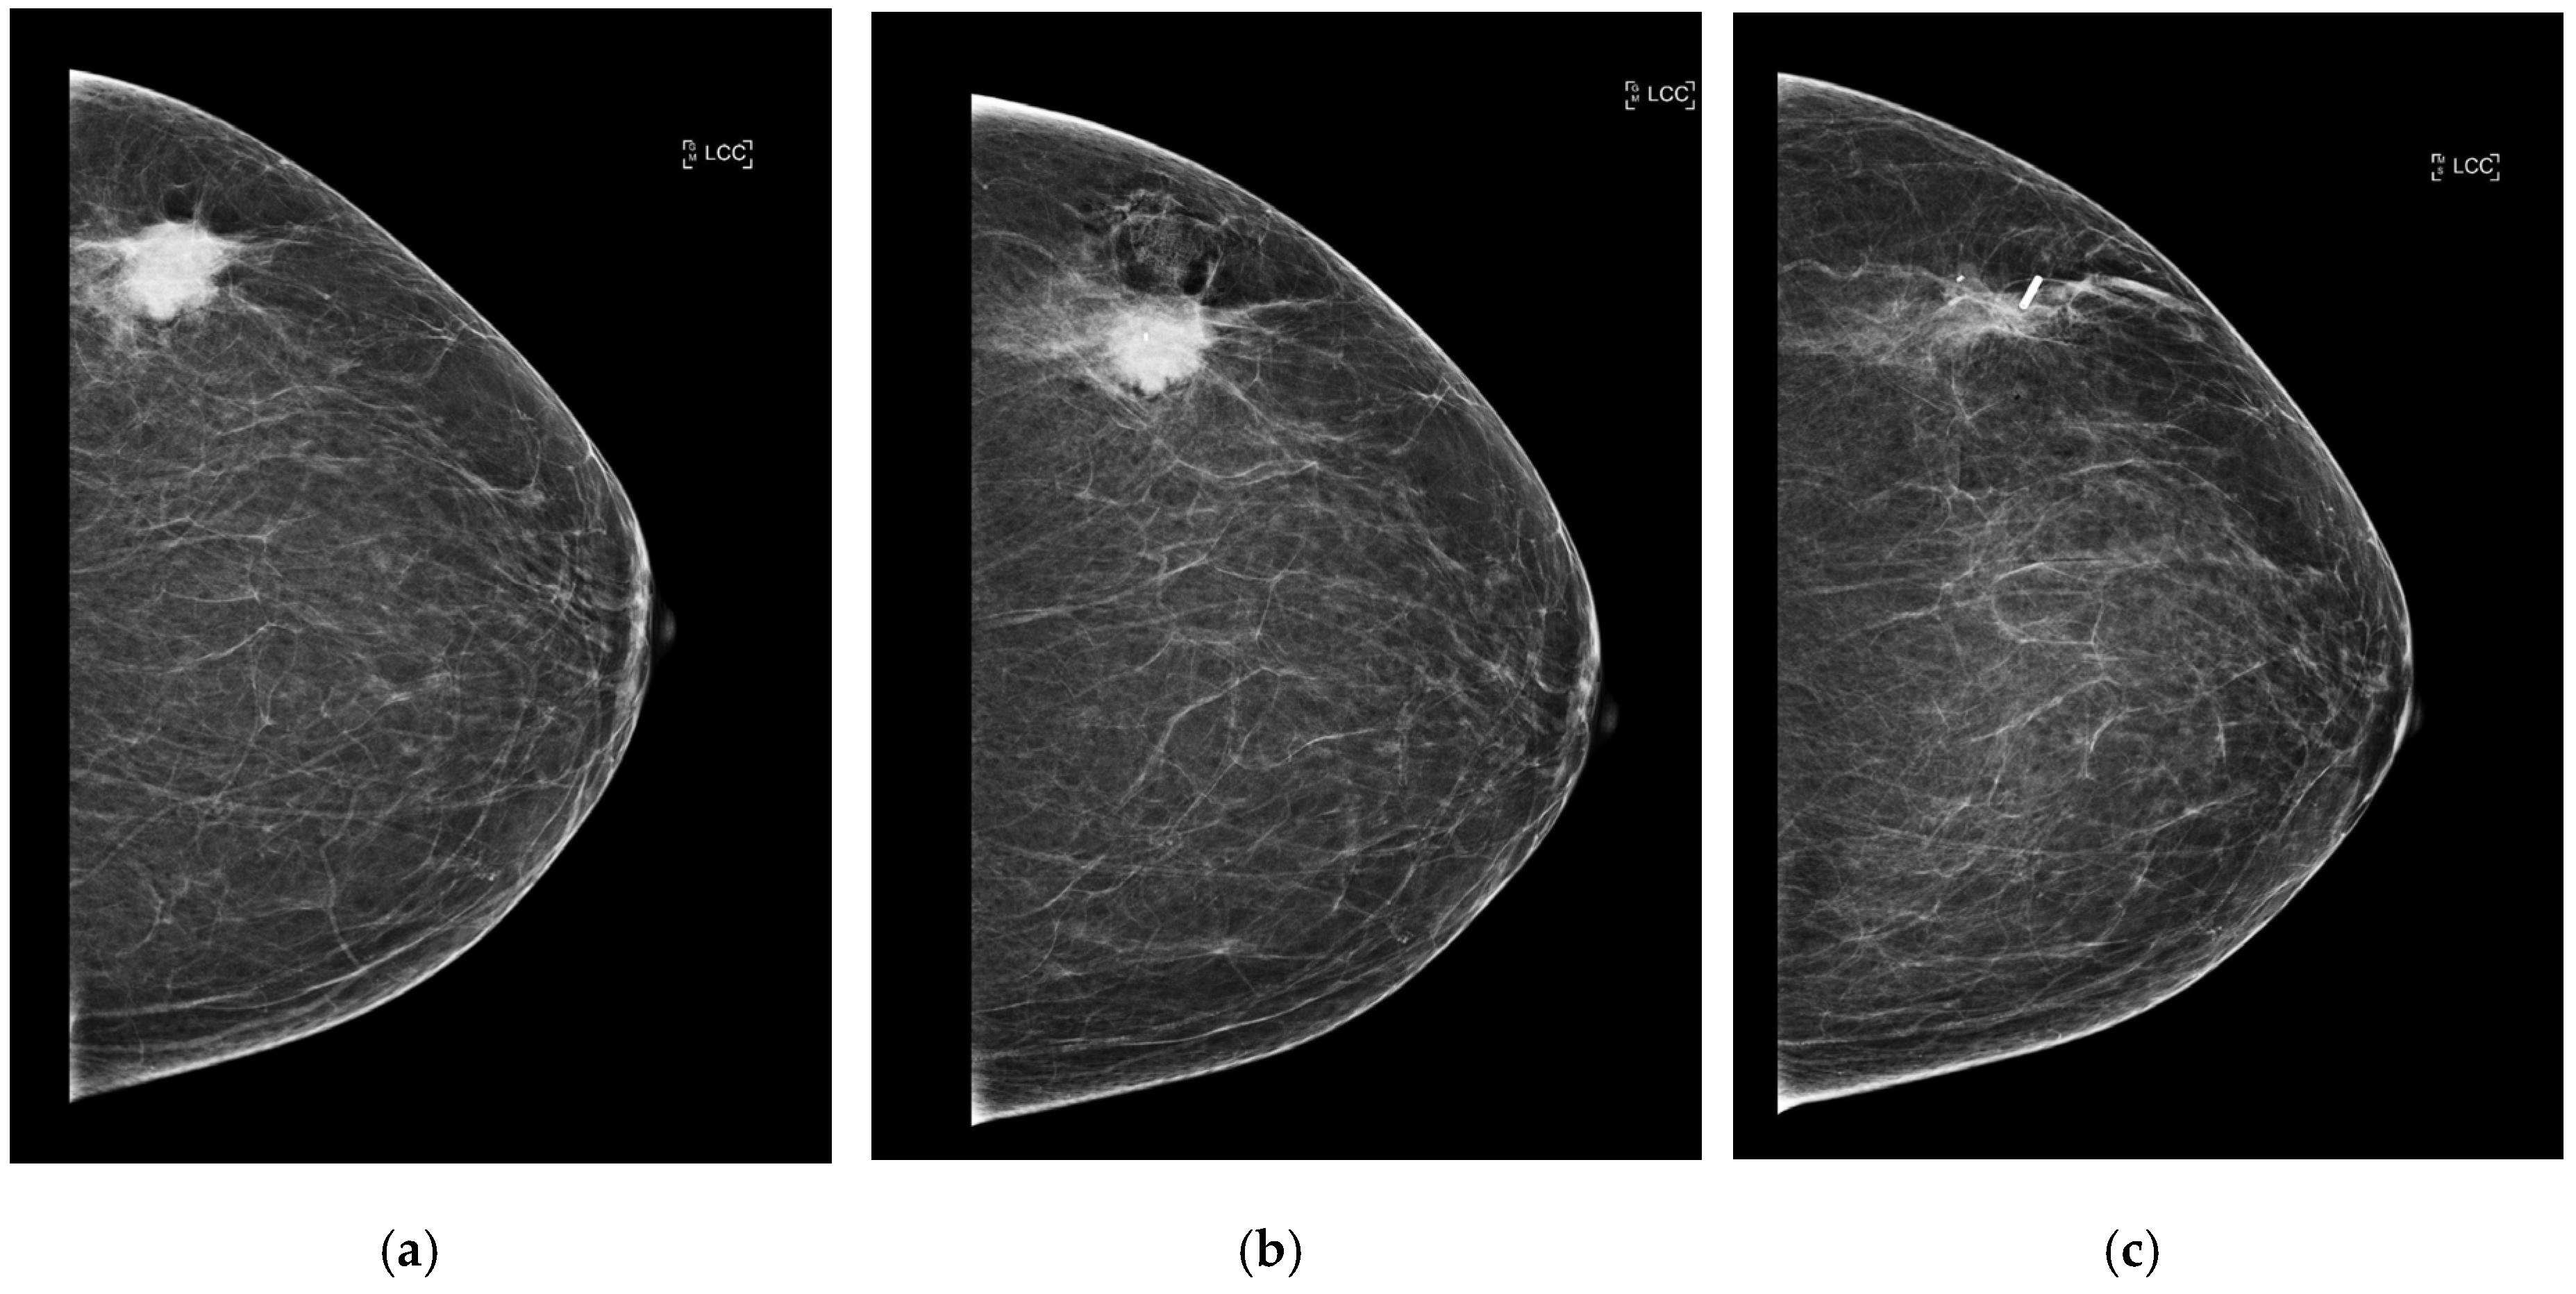

After placement, standard two-view mammograms were obtained to confirm RFID tag placement. Placement accuracy was recorded by measuring the shortest distance, on either the mediolateral oblique (MLO) or craniocaudal (CC) view, from the RFID tag to the intended target (e.g., target lesion, distortion, MCC) on the post-clip mammograms. Following surgical excision, a specimen radiograph was performed to confirm RFID tag presence and location (Figure 3a–c and Figure 4). Additionally, any cases of RFID tag migration were documented, along with factors such as hematoma formation or lesion characteristics that may have influenced RFID tag positioning. Data collection was conducted in compliance with institutional ethical guidelines, ensuring patient confidentiality and adherence to research standards.

Figure 3. (a) Craniocaudal (CC) view of the left breast of predominately fat density (BI-RADS A). There is a 27 mm malignant-appearing mass in the upper portion of the left breast. (b) CC post-biopsy mammogram shows the marker clip within the center of the lesion. Following ultrasound-guided core needle biopsy and accurate clip placement, biopsy results yielded invasive ductal carcinoma (grade 3). The patient underwent neo-adjuvant chemotherapy followed by radiofrequency RFID tag localization. (c) CC view of the left breast. The known mass within the upper outer quadrant has reduced in size following neo-adjuvant chemotherapy and measures 19 mm (from 27 mm initially). The post-localization mammogram shows successful RFID tag placement (at the lateral aspect of the lesion).